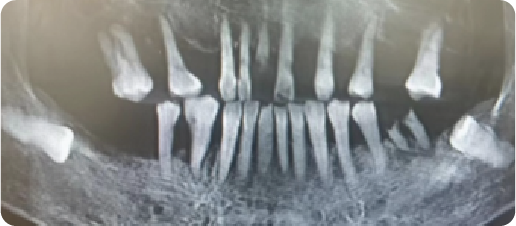

Case of Multiple Missing Teeth with Mobility of the Residual Dentition

BEFORE

VS

AFTER

Name:Mr NiuAge:64

Evaluation: Generalized tooth mobility and multiple tooth loss secondary to poor periodontal status

Treatment Plan:Two implants were placed in both the maxillary and mandibular anterior regions, each supporting two crowns, restoring a total of four teeth, a three unit fixed bridge, with a pontic for tooth #5, was supported by two implants in positions #4 and #6 in the upper left quadran.

Patient Feedback:It feels solid—I can bite with confidence, My healthy teeth were left alone, and they look so natural and feel so comfortable, it's just like having my own teeth back.